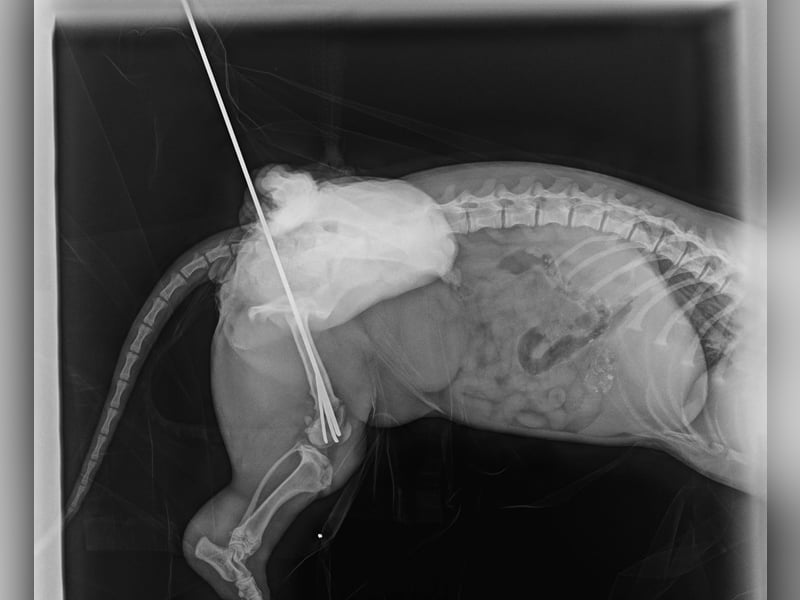

Ilse hatte einmal eine Besitzerin, doch ihr Leben war nicht leicht. Als sie aus dem Hof entkam, wurde sie von einem Auto angefahren und brach sich ein Bein. Zum Glück konnte sie operiert werden – die OP war erfolgreich, und Ilse läuft und rennt wieder ganz normal! Die Metallstifte werden in Kürze entfernt.